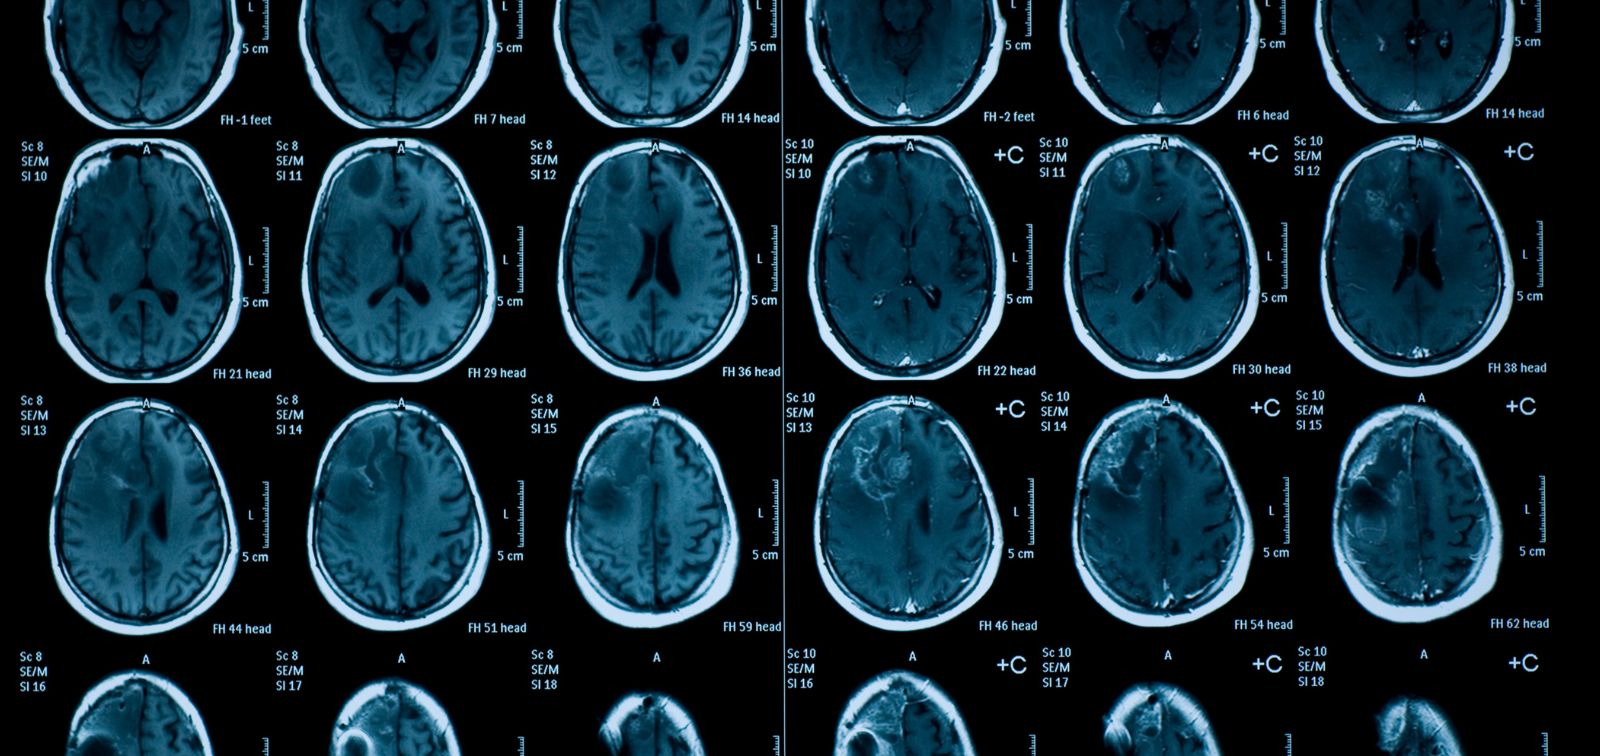

The study involved 2,229 children aged 9 to 12 from the “Generation R” cohort in Rotterdam, Netherlands. Functional connectivity data from brain networks, i.e., how different regions of the brain communicate and collaborate, were assessed using resting-state magnetic resonance imaging, when the children were not performing any active tasks. Daily mean temperature estimates were obtained from the UrbClim urban climate model, developed by the Flemish Institute for Technological Research. Temperature values were calculated for the period from 2013 to 2015, assigning daily averages to each participant based on their home address.

Higher ambient temperatures during the week preceding the MRI assessment were associated with lower functional connectivity within the medial parietal, salience, and hippocampal networks, which are essential for proper brain functioning. This implies that brain areas may work less synchronously, affecting processes such as attention, memory, and decision-making. The medial parietal network is related to introspection and self-perception; the salience network detects environmental stimuli and prioritizes what deserves our attention; and the hippocampal network is critical for memory and learning.